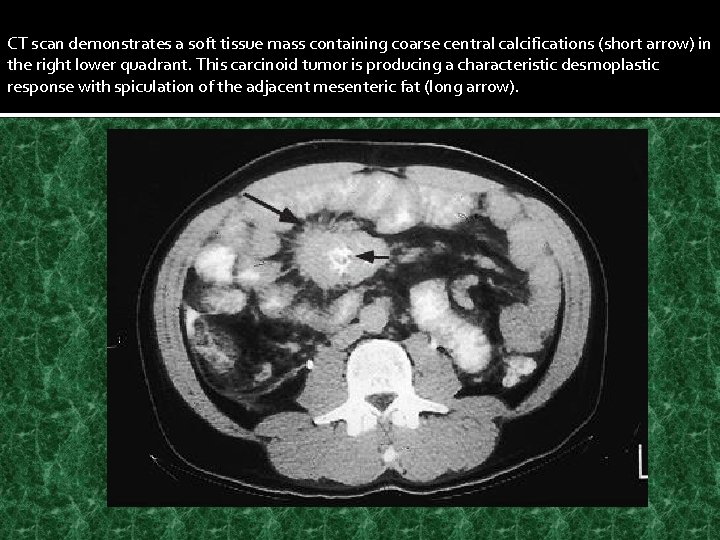

CT scan demonstrates a soft tissue mass containing coarse central calcifications (short arrow) in the right lower quadrant. This carcinoid tumor is producing a characteristic desmoplastic response with spiculation of the adjacent mesenteric fat (long arrow).